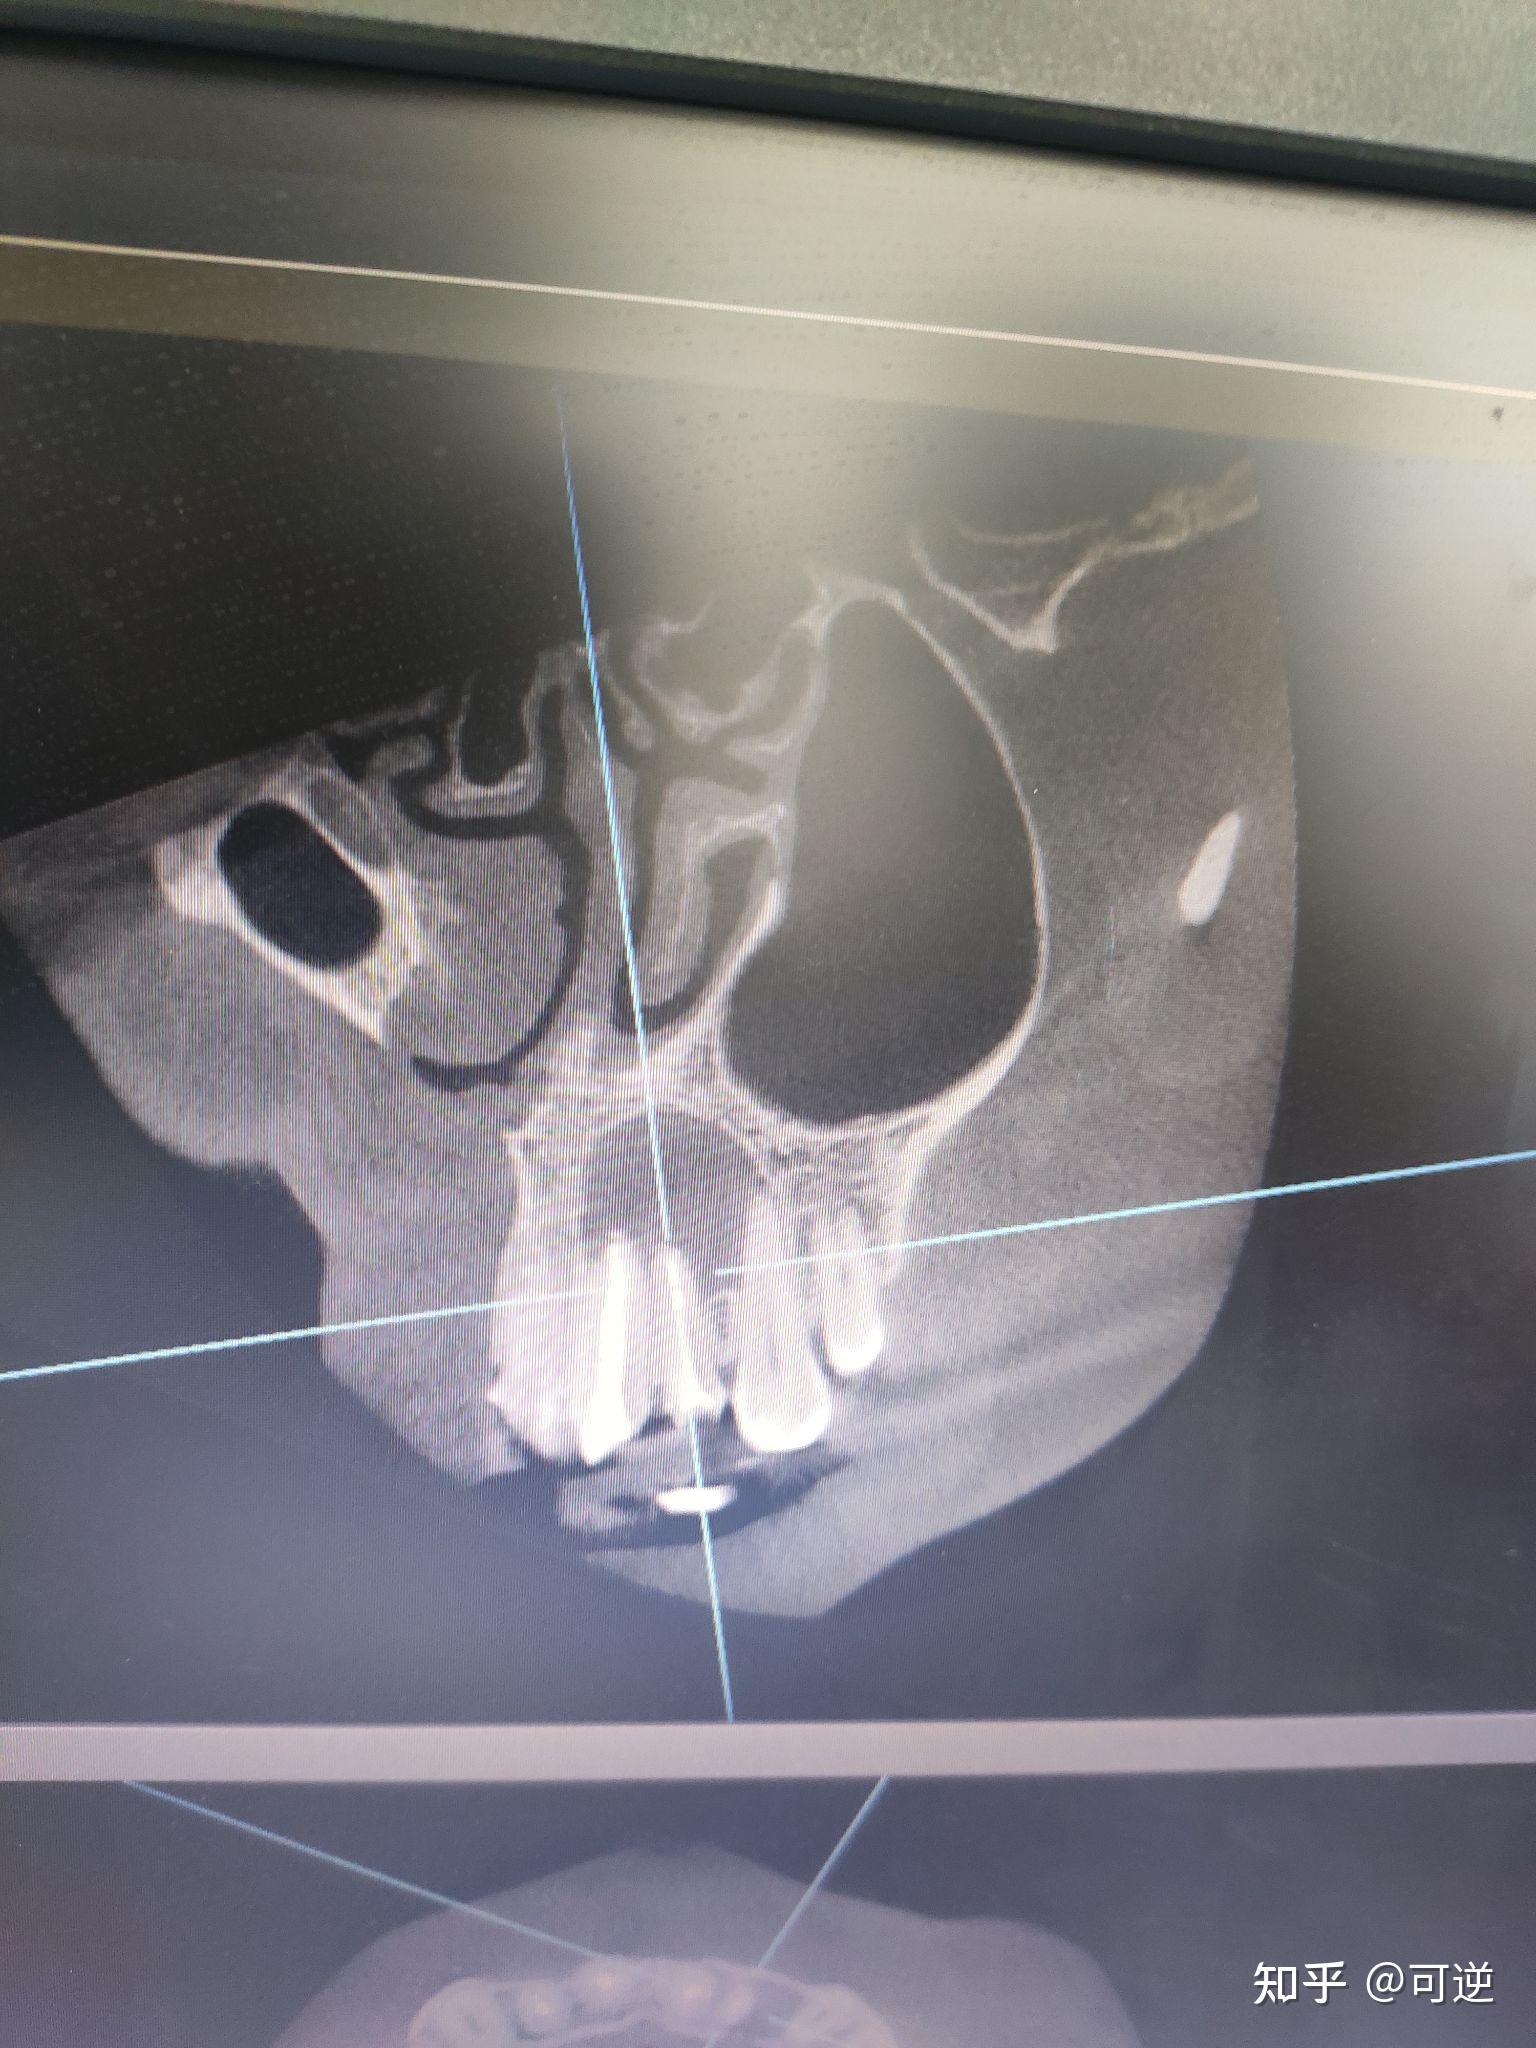

cbct检查 前牙区囊肿

图片尺寸2667x2000